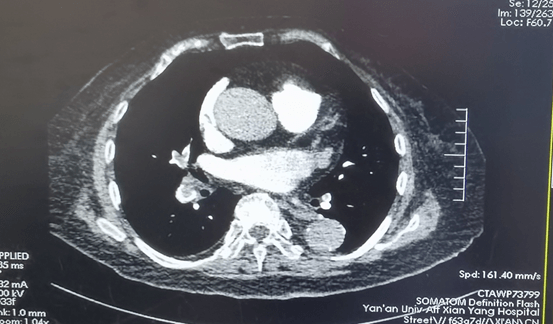

到達(dá)我院后,值班醫(yī)生黃永濤查看患者后,發(fā)現(xiàn)她嗜睡狀態(tài),查體發(fā)現(xiàn)呼吸急促、皮膚黏膜發(fā)紺、心動(dòng)過速、雙下肢腫脹,患者血氧飽和度只有46mmHg,血壓:135/80mmhg,脈搏:102次/分;黃醫(yī)生判斷患者病情危重,考慮肺栓塞可能,遂請(qǐng)示科主任崔旭輝主任醫(yī)師。指示:立即完善血?dú)夥治觥-二聚體、肺動(dòng)脈CT造影、下肢深靜脈超聲等檢查等。結(jié)果回報(bào)D-二聚體顯著升高至7.09ug/ml,雙側(cè)股總靜脈游離血栓形成、雙肺多發(fā)肺栓塞,進(jìn)一步證明了肺栓塞的診斷?;颊弑涣⒓此屯鵆CU呼吸機(jī)輔助呼吸并積極抗凝治療。